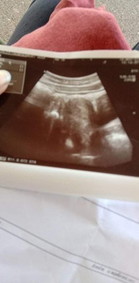

มีแม่ๆคนไหนเคยมีอาการบ้างคะ อายุครรภ์หนูยังอ่อนมากค่ะ หมอซาวค์ บอกไม่เจอการตั้งครรภ์ในมดลูก แต่ตรวจภายใน ปากมดลูกปิดอยู่ค่ะ อาการคือมีเลือดออกซิบๆ แล้วก็หาย ปวดท้องน้อยฝั่งขวาเป็นระยะ อาการปวดคงที่ หมอให้ยาบำรุงเลือดมาทานค่ะ และสั่งไม่ให้ลุกเดินบ่อย ไม่ให้ขยับบ่อยค่ะ ตอนนี้คือรออายุครรภ์มากกว่านี้ค่ะ ลุ้นว่าน้องหลุดหรือน้องยังอยู่ค่ะ😭😭😭😭#ขอคำแนะนำหน่อยค่ะ #ขอบคุณล่วงหน้านะคะ #ขอบคุณล่วงหน้านะคะ #ท้องแรกคะ #ขอบคุณสำหรับคำตอบค่ะ #ใครมีประสบการณ์ #คุณแม่ๆช่วยแนะนำหน่อยค่ะ